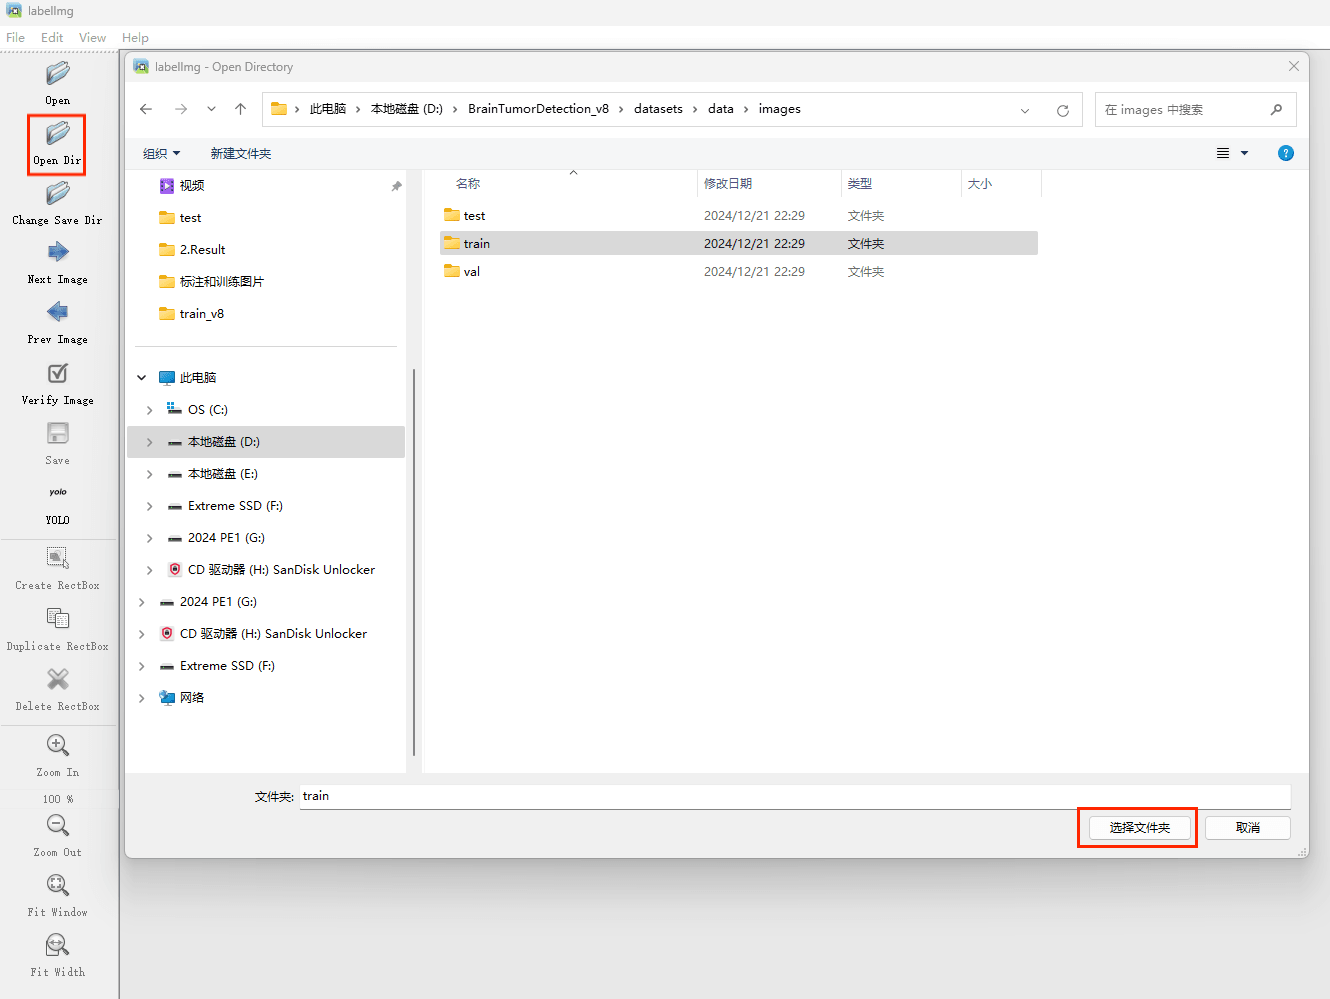

接下来我们打开需要标注的图片文件夹

(3)数据准备

这里建议新建一个名为data的文件夹(这个是约定俗成,不这么做也行),里面创建一个名为images的文件夹存放我们需要打标签的图片文件;再创建一个名为labels存放标注的标签文件;最后创建一个名为 classes.txt 的txt文件来存放所要标注的类别名称。

data的目录结构如下:

首先在images这个文件夹放置待标注的图片。